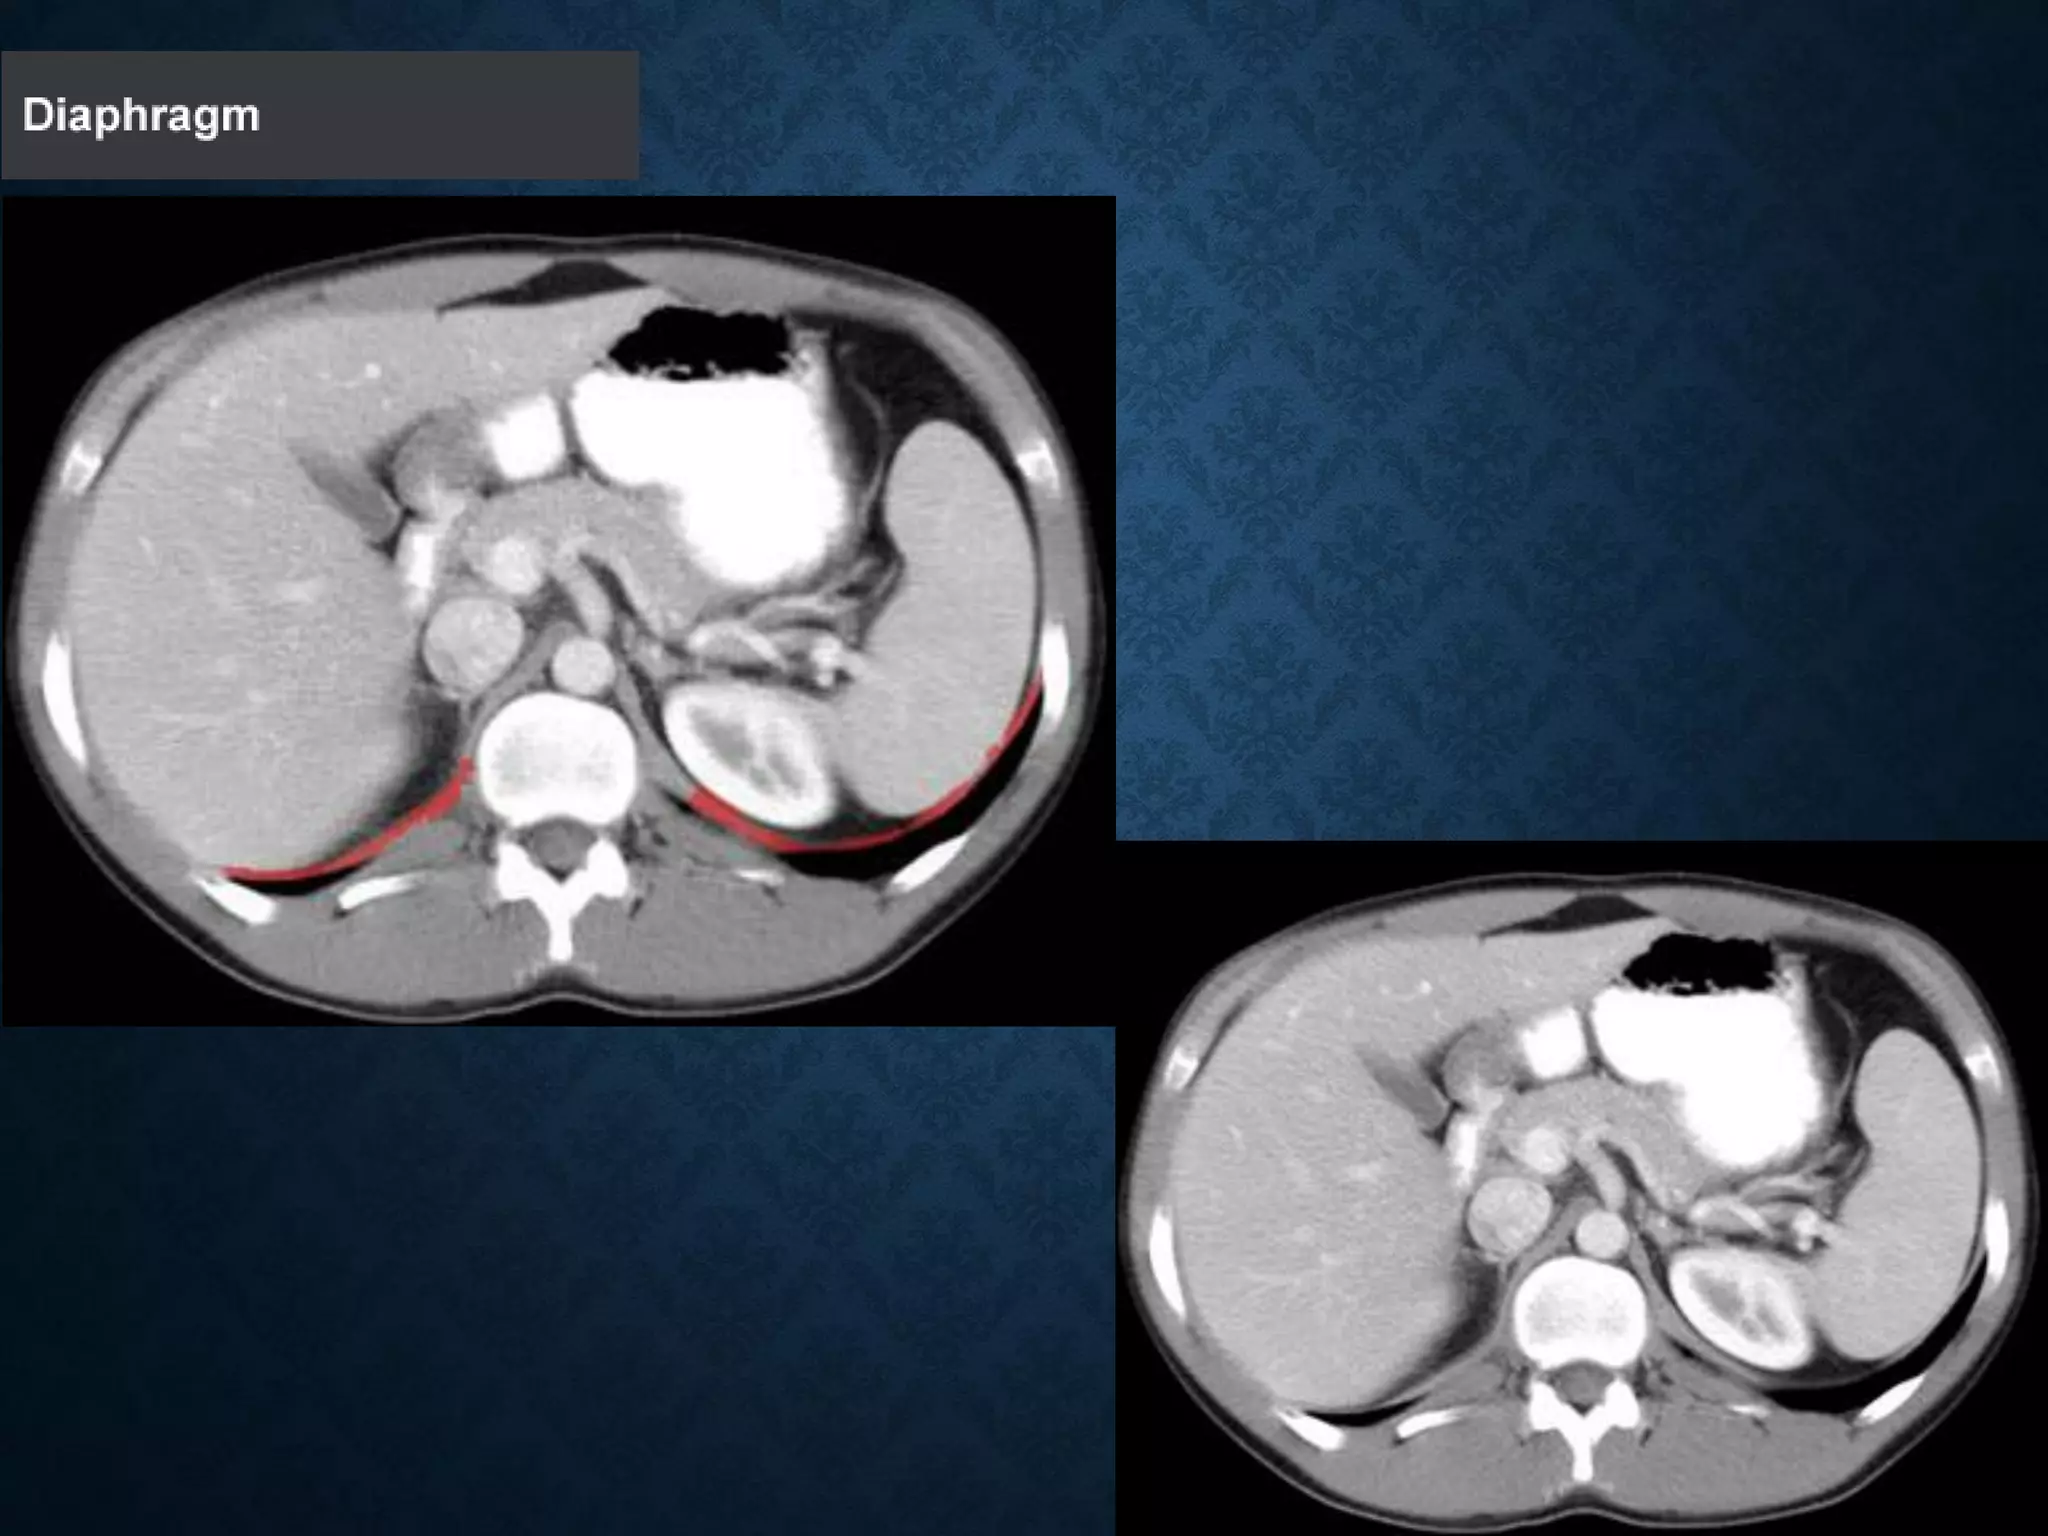

Identify the following structures in the body CT to the right. To view the location of the structure in the image click on

the label at the left and the structure will be indicated in the image. Abdominal CT scans typically begin just above

the diaphragm, so the first slice you see is of the lower chest.

Identify the followingstructures in the body CT to the right. To view the location of the structure in the image click on the label at the left and the structure will be indicated in the image. Abdominal CT scans typically begin just above the diaphragm, so the first slice you see is of the lower chest.